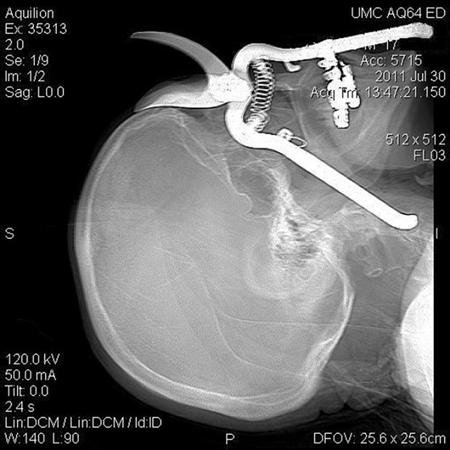

Arizona man impaled through skull with pruning shears

TUCSON, Ariz (Reuters) - An 86-year-old Arizona man who was impaled through the skull with pruning shears in a freak gardening accident was expected to make a full recovery, his doctors said.

Leroy Luetscher dropped a pair of pruning shears while working in his yard in Green Valley, south of Tucson, on July 30, the University Medical Center in Tucson said in a news release.

The shears landed in the ground point downward. When Luetscher bent down to pick them up, he overbalanced and fell face-down on the handle, which punched through his eye socket and went down into his neck.

Luetscher was rushed by ambulance to University Medical Center in Tucson, where a team of surgeons were able to remove the shears, rebuild the eye socket with metal mesh, and save his eye.

"You wouldn't believe your eyes," said Julie Wynne, a trauma surgeon who was part of the team that operated on Luetscher. "Half of the pruning shears was sticking out and the other half was in his head."

An X-ray photograph released by the University Medical Center showed a shadow image of the shears embedded in Luetscher's skull, with the blade resting flush against his forehead.

"You just wonder how the handle of the pruning shears got there. The handle was actually resting on the external carotid artery in his neck," said Lynn Polonski, a clinical assistant professor of ophthalmology.